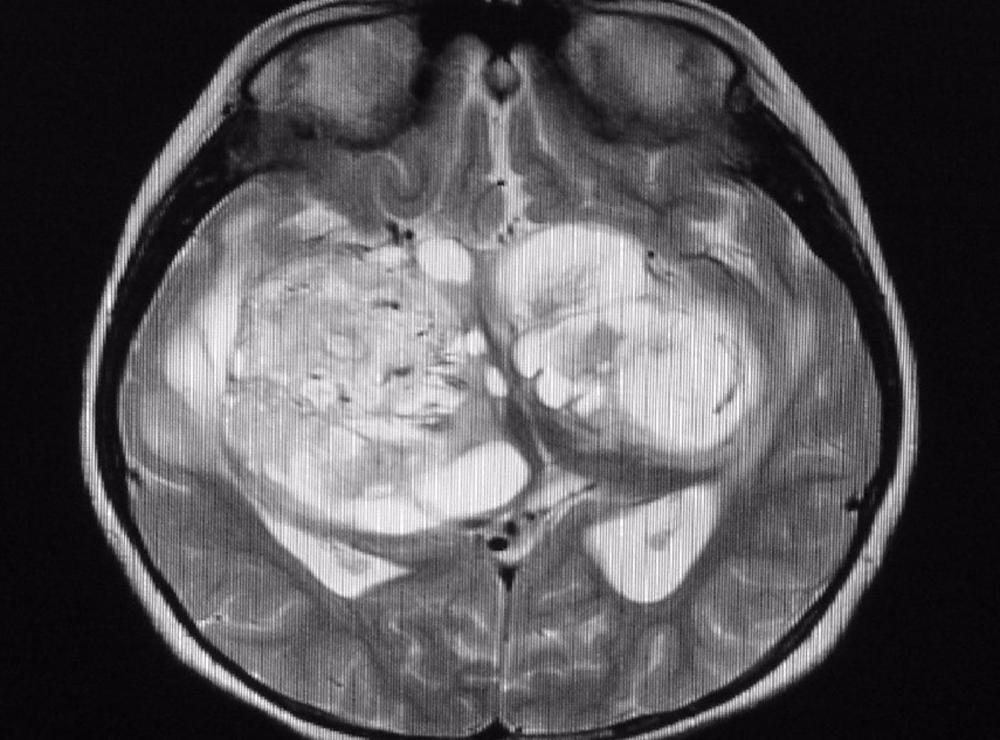

Un estudio internacional codirigido por la Universidad de California (UCLA) ha descubierto que el fármaco vorasidenib duplica con creces la supervivencia libre de progresión en personas con glioma recurrente de grado 2 con mutaciones IDH1 e IDH2, un tipo de tumor cerebral mortal, retrasando el momento de empezar con quimioterapia o radioterapia.

El glioma recurrente de grado 2 con mutaciones IDH1 e IDH2, tiende a afectar a las personas más jóvenes, a menudo a los 30 años. El tratamiento estándar actual, una combinación de radiación y quimioterapia, puede causar déficits neurológicos que dificultan que los pacientes aprendan, recuerden cosas nuevas, se concentren o tomen decisiones cotidianas, todo lo cual puede ser especialmente desafiante para las personas que tienen familias jóvenes.